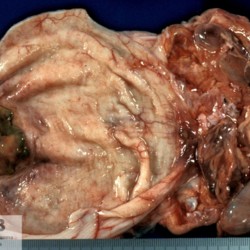

Etiquetes: N-399/92 1 total General Specie: General Organ: Urinay bladder Lesion: Cystitis Lesion modifier: Cystitis - Necrotizing Disease: - Files/Expedient: N-399/92 Not viewed Títol Select...Avian (Exotic) (110)Avian (Poultry) (76)Bovine (317)Canine (935)Caprine (47)Equine (257)Feline (326)Ferret (19)General (127)Marine mammal (22)Non-human primate (20)Ovine (328)Porcine (379)Rabbit (61)Reptile (38)Rodent (28)Wildlife (91) Format Select...- (60)Abomasum (37)Adrenal gland (10)Blood (7)Blood vessel (50)Body as a whole (19)Bone (57)Bone marrow (21)Brain (93)Cloaca (1)Diaphragm (2)Ear (5)Esophagus (39)Eye (16)Fetus (12)Gallbladder (23)Gizzard (2)Heart (265)Intestine (356)Joint (32)Kidney (443)Larynx (5)Liver (326)Lung (264)Lymph node (91)Mammary gland (10)Mediastinum (1)Muscle (22)Nasal cavity (22)Nerve (7)Omasum (5)Oral cavity (63)Ovary (14)Oviduct (8)Pancreas (7)Parathyroid (5)Penis (10)Peritoneum (65)Pharynx (9)Pituitary gland (6)Placenta (7)Prostate (8)Proventriculus (3)Reticulum (1)Rumen (28)Sinus (7)Skin (181)Spinal cord (15)Spleen (105)Stomach (125)Teeth (1)Testicle (11)Thoracic cavity (31)Thymus (13)Thyroid gland (5)Tongue (32)Tonsils (11)Trachea (11)Urethra (5)Urinay bladder (61)Uterus (27)Vagina (1)Vulva (1)Yolk sac (1) Cobertura Select...- (152)Abomasitis (26)Abscess (27)Acidosis (1)Adenocarcinoma (20)Adenoma (9)Aerosacculitis (6)Agenesis (1)Agnathia (1)Alopecia (7)Amyloidosis (12)Aneurysm (6)Angiectasis (1)Anthracosis (1)Arteritis (11)Arthritis (15)Arthrogryposis (6)Artifact (4)Ascites (13)Atelectasis (8)Atherosclerosis (5)Atresia (1)Atrial septal defect (2)Atrophy (10)Autolysis (7)Bronchitis (6)Bronchopneumonia (26)Cachexia (2)Carcinoma (103)Cardiomyopathy (19)Cellulitis (2)Chemodectoma (4)Cholangiohepatitis (4)Cholangitis (19)Cholecystitis (4)Cholestasis (5)Chondrodysplasia (2)Chondrosarcoma (2)Chronic passive congestion (13)Chylothorax (2)Cirrhosis (6)Coelomitis (3)Coenurus cerebralis (4)Colitis (40)Congestion (17)Conjunctivitis (5)Coronitis (3)Cryptorchidism (3)Cyst (25)Cystitis (24)Dermatitis (69)Diaphragmatic hernia (4)Dilation (28)Discospondylitis (1)Disseminated intravascular coagulation (7)Dyschondroplasia (1)Dysplasia (29)Ectopia cordis (1)Ectopic ureter (1)Edema (55)Emphysema (5)Encephalitis (5)Endocardiosis (14)Endocarditis (26)Endometritis (5)Enteritis (118)Enterolith (6)Epulis (3)Esophagitis (14)Fasciitis (1)Fibrosis (7)Fibrous osteodystrophy (8)Fistula (1)Folliculitis (3)Fracture (2)Gastritis (34)Gingivitis (5)Glioma (8)Glomerulonephritis (21)Glossitis (25)Glycogenosis (1)Gout (8)Granuloma (2)Granulosa cell tumor (4)Hemangioma (9)Hemangiosarcoma (46)Hematoma (8)Hemoglobinuria (2)Hemopericardium (12)Hemoperitoneum (2)Hemorrhage (100)Hemosiderosis (7)Hemothorax (2)Hepatitis (78)Hernia (11)Histiocytosis (3)Hydatid cyst (11)Hydrocephalus (9)Hydrometra (1)Hydronephrosis (22)Hydropericardium (6)Hydrothorax (3)Hydroureter (5)Hyperkeratosis (8)Hyperostosis (4)Hyperplasia (37)Hypertrophy (9)Hypopigmentation (1)Hypoplasia (7)Hypopyon (1)Impaction (6)Infarction (63)Insulinoma (6)Intussusception (5)Jaundice (17)Laminitis (2)Laryngitis (2)Leiomyoma (5)Leukemia (13)Lipidosis (36)Lipoma (7)Lymphadenitis (45)Lymphadenopathy (7)Lymphangiectasia (6)Lymphangitis (5)Lymphoma (221)Malacia (11)Malignant melanoma (15)Mast cell tumor (11)Mastitis (8)Megaesophagus (2)Melanosis (3)Melena (4)Meningioma (6)Meningitis (6)Meningocele (2)Meningoencephalitis (5)Mesothelioma (5)Methemoglobinemia (2)Mineralization (10)Mucocele (5)Mucometra (1)Multilobular bone tumor (1)Mummification (3)Myelofibrosis (1)Myocarditis (4)Myositis (5)Necrosis (81)Nephritis (113)Nephroblastoma (6)Nephrosclerosis (1)Nephrosis (14)Neuritis (1)Obstruction (13)Omasitis (4)Omphalitis (1)Omphalophlebitis (7)Orchitis (4)Osteoarthrosis (5)Osteomyelitis (9)Otitis (2)Palatoschisis (3)Pancreatitis (3)Panniculitis (3)Papilloma (7)Parakeratosis (14)Patent ductus arteriosus (6)Peliosis hepatis (1)Perforation (17)Pericarditis (35)Peritonitis (39)Persistent right aortic arch (1)Pharyngitis (2)Pheochromocytoma (2)Phlebitis (2)Placentitis (6)Pleuritis (21)Pleuropneumonia (24)Pneumonia (109)Pneumothorax (3)Polycystosis (14)Polyp (5)Polyserositis (6)Posthitis (1)Proctitis (4)Prolapse (3)Prostatitis (3)Proventriculitis (1)Pyelonephritis (24)Pyometra (6)Pyothorax (4)Rhinitis (11)Rumenitis (6)Rupture (24)Salpingitis (3)Sarcoma (57)Sclerosis (1)Scoliosis (2)Seminoma (2)Sequestrum (2)Serous atrophy (14)Sinusitis (7)Splenitis (14)Splenomegaly (9)Spondylitis (6)Spondylosis (1)Stenosis (9)Stomatitis (32)Tenosynovitis (2)Teratoma (3)Thricobezoar (2)Thrombosis (16)Tonsilitis (4)Torsion (13)Tracheitis (4)Tympany (7)Typhlitis (8)Typhlocolitis (4)Ulcer (43)Urethritis (1)Urolithiasis (36)Uroperitoneum (1)Uveitis (1)Vasculitis (15)Ventricular septal defect (3)Volvulus (11) Matèria Select... - (14)- (1653)- (152)Abomasitis - Catarrhal (2)Abomasitis - Catarrhal-hemorrhagic (1)Abomasitis - Chronic (1)Abomasitis - Fibrinous-necrotizing (2)Abomasitis - Hyperplasic (5)Abomasitis - Hyperplasic - Chronic (1)Abomasitis - Necrotic (1)Abomasitis - Necrotizing (2)Abomasitis - Ulcerative (5)Adenocarcinoma (9)Aerosacculitis - Granulomatous (1)Amyloidosis - Chronic (1)Arteritis - Necrotic (2)Arteritis - Necrotizing (1)Arthritis - Chronic (4)Arthritis - Fibrinous-purulent (3)Arthritis - Serous (4)Arthritis - Subacute (1)Ascites - Serous (1)Atrophy - Serous (1)Bronchitis - Catarrhal (3)Bronchitis - Suppurative (1)Bronchopneumonia - Catarrhal-purulent (17)Bronchopneumonia - Fibrinous (1)Bronchopneumonia - Granulomatous (1)Bronchopneumonia - Purulent (1)Bronchopneumonia - Suppurative (5)Carcinoma - Adenocarcinoma (33)Carcinoma - Adenocarcinoma - Hepatocellular (2)Carcinoma - Adenocarcinoma - Mucinous (1)Carcinoma - Basosquamous (1)Carcinoma - Cholangiocellular (3)Carcinoma - Hepatocellular (4)Carcinoma - Metastatic (3)Carcinoma - Squamous cell carcinoma (13)Carcinoma - Transitional cell (2)Cardiomyopathy - Dilated (13)Cardiomyopathy - Hypertrophic (6)Cellulitis - Necrotizing (1)Cholangitis - Chronic (8)Cholangitis - Hyperplasic (3)Cholecystitis - Fibrinous-necrotizing (1)Coelomitis - Fibrinous (1)Coelomitis - Granulomatous (1)Colitis - Catarrhal (3)Colitis - Catarrhal-hemorrhagic (1)Colitis - Fibrinous (1)Colitis - Fibrinous-necrotizing (1)Colitis - Fibrinous-necrotizing (Diphtheritic) (6)Colitis - Granulomatous (2)Colitis - Hemorrhagic (4)Colitis - Hemorrhagic-necrotizing (3)Colitis - Necrotizing (2)Colitis - Ulcerative (6)Congestion - Chronic (2)Conjunctivitis - Hyperplasic (1)Conjunctivitis - Purulent (3)Coronitis - Ulcerative (1)Cystitis - Chronic (3)Cystitis - Fibrinous (1)Cystitis - Fibrinous-necrotizing (1)Cystitis - Follicular (1)Cystitis - Hemorrhagic (6)Cystitis - Hemorrhagic-ulcerative (1)Cystitis - Necrotizing (9)Cystitis - Perforated (1)Dermatitis - Granulomatous (14)Dermatitis - Hyperkeratotic (10)Dermatitis - Hyperplasic (proliferative) (1)Dermatitis - Hyperplastic (10)Dermatitis - Necrotizing (4)Dermatitis - Pustular (4)Dermatitis - Ulcerative (2)Dilation - Chronic (1)Discospondylitis - Necrotizing (1)Dysplasia - Follicular (5)Edema - Interstitial (6)Emphysema - Interstitial (1)Encephalitis - Granulomatous (1)Encephalitis - Nonsuppurative (1)Endocardiosis - Mitral (7)Endocardiosis - Mitral - Chronic (5)Endocarditis - Valvular (6)Endocarditis - Valvular - Mitral (7)Endocarditis - Valvular - Pulmonic (1)Endocarditis - Valvular - Subacute (1)Endocarditis - Valvular - Subaortic (5)Endocarditis - Valvular - Tricuspid (4)Endometritis - Purulent (3)Endometritis - Purulent-hemorrhagic (2)Enteritis - Catarrhal (23)Enteritis - Catarrhal - Acute (1)Enteritis - Catarrhal-hemorrhagic (5)Enteritis - Catarrhal-hemorrhagic - Acute (2)Enteritis - Fibrinous (16)Enteritis - Fibrinous - Acute (3)Enteritis - Fibrinous-necrotizing (7)Enteritis - Granulomatous (14)Enteritis - Granulomatous - Chronic (1)Enteritis - Granulomatous - Multifocal (1)Enteritis - Hemorrhagic (17)Enteritis - Hemorrhagic - Acute (1)Enteritis - Hemorrhagic-necrotizing (1)Enteritis - Hyperplasic (proliferative) (4)Enteritis - Necrotizing (4)Enteritis - Necrotizing - Acute (1)Enteritis - Necrotizing - Hemorrhagic (1)Enteritis - Necrotizing-ulcerative (2)Enteritis - Ulcerative (1)Enteritis - Ulcerative-hemorrhagic (1)Esophagitis - Erosive-ulcerative (6)Esophagitis - Necrotizing (4)Esophagitis - Ulcerative (1)Esophagitis - Ulcerative-necrotizing (1)Fasciitis - Fibrinous-purulent (1)Folliculitis - Purulent (2)Gastritis - Catarrhal (2)Gastritis - Chronic (1)Gastritis - Follicular (1)Gastritis - Hemorrhagic (2)Gastritis - Hemorrhagic-necrotizing (1)Gastritis - Hypertrophic (2)Gastritis - Inclusion bodies (1)Gastritis - Mineralization (1)Gastritis - Mycotic (1)Gastritis - Necrotizing (2)Gastritis - Ulcerative (6)Gastritis - Uremic (3)Gingivitis - Erosive (2)Gingivitis - Hyperplasic (proliferative) (1)Gingivitis - Necrotizing (1)Glomerulonephritis - Chronic (7)Glomerulonephritis - Membranoproliferative (3)Glomerulonephritis - Membranoproliferative - Chronic (1)Glomerulonephritis - Membranous (3)Glomerulonephritis - Membranous - Chronic (1)Glomerulonephritis - Proliferative (2)Glomerulonephritis - Subacute (1)Glossitis - Erosive (2)Glossitis - Granulomatous (6)Glossitis - Hyperplasic (1)Glossitis - Hyperplasic (proliferative) (2)Glossitis - Hyperplastic (1)Glossitis - Necrotizing (2)Glossitis - Necrotizing - Focal (1)Glossitis - Ulcerative (6)Glossitis - Ulcerative - Multifocal (1)Glossitis - Ulcerative - Subacute (1)Glycogenosis (1)Granuloma - Eosinophilic (1)Hemangiosarcoma - Metastatic (2)Hemorrhage - Acute (1)Hemorrhage - Subcapsular (3)Hepatitis - Abscess (9)Hepatitis - Acute (3)Hepatitis - Chronic (4)Hepatitis - Chronic interstitial (6)Hepatitis - Granulomatous (7)Hepatitis - Interstitial - Multifocal (1)Hepatitis - Interstitial - Subacute (1)Hepatitis - Necrotizing (17)Hepatitis - Necrotizing - Acute (2)Hepatitis - Necrotizing - Hemorrhagic (1)Hepatitis - Necrotizing - Subacute (1)Hepatitis - Pyogranulomatous (7)Hepatitis - Subacute (4)Hydronephrosis - Chronic (1)Hydropericardium - Chronic (1)Hyperplasia - Erythroid (1)Hyperplasia - Lymphoid (3)Hyperplasia - Myeloid (1)Hyperplasia - Nodular (8)Hypertrophy - Concentric (2)Hypertrophy - Eccentric (3)Infarction - Acute (17)Infarction - Acute - Multifocal (2)Infarction - Chronic (5)Infarction - Chronic - Multifocal (1)Infarction - Subacute (18)Infarction - Subacute - Focal (2)Laminitis - Chronic (2)Laryngitis - Necrotic (1)Laryngitis - Necrotizing (1)Leukemia - Lymphoid leukemia (2)Leukemia - Non-lymphoid leukemia (6)Lipidosis - Multifocal (1)Lipidosis - Panlobular (1)Lipidosis - Panlobular - Generalized (2)Lymphadenitis - Granulomatous (24)Lymphadenitis - Granulomatous - Chronic (3)Lymphadenitis - Hemorrhagic (1)Lymphadenitis - Necrotizing (5)Lymphadenitis - Necrotizing (caseous) (11)Lymphangitis - Granulomatous (1)Lymphangitis - Purulent (1)Lymphangitis - Ulcerative (1)Lymphoma - Alimentary lymphoma (7)Lymphoma - Cutaneous lymphoma (6)Lymphoma - Lymphosarcoma (2)Lymphoma - Mediastinal lymphoma (1)Lymphoma - Multicentric lymphoma (29)Malignant melanoma - Malignant (1)Malignant melanoma - Metastatic (1)Mast cell tumor - Metastatic (1)Mastitis - Fibrinous-purulent (2)Mastitis - Necrotic (1)Mastitis - Purulent (3)Mastitis - Suppurative (1)Meningitis - Fibrinous-purulent (2)Meningitis - Purulent (4)Meningoencephalitis - Necrotizing (3)Meningoencephalitis - Nonsuppurative (2)Mineralization - Metastatic (4)Myocarditis - Fibrous - Chronic (1)Myocarditis - Granulomatous (1)Myositis - Purulent (2)Necrosis - Acute (1)Necrosis - Cortical (5)Necrosis - Follicular (1)Necrosis - Papillary (8)Necrosis - Papillary - Acute (3)Necrosis - Subacute (3)Necrosis - Tubular (6)Nephritis - Embolic (2)Nephritis - Embolic suppurative (7)Nephritis - Granulomatous (27)Nephritis - Granulomatous - Chronic (1)Nephritis - Granulomatous - Multifocal (1)Nephritis - Interstitial (6)Nephritis - Interstitial - Acute (4)Nephritis - Interstitial - Chronic (41)Nephritis - Interstitial - Subacute (12)Nephritis - Purulent (7)Nephritis - Purulent - Acute (2)Nephritis - Purulent - Multifocal (3)Nephrosis - Cholemic (3)Nephrosis - Hemoglobinuric (10)Omasitis - Fibrinous-necrotizing (1)Omasitis - Hyperkeratotic (1)Omasitis - Necrotizing (2)Omphalophlebitis - Fibrinous-purulent (2)Omphalophlebitis - Purulent (3)Orchitis - Necrotizing (1)Osteomyelitis - Necrotizing (7)Osteomyelitis - Purulent (2)Otitis - Necrotizing (1)Otitis - Proliferative (1)Pancreatitis - Acute (1)Pancreatitis - Chronic (1)Pancreatitis - Granulomatous (1)Panniculitis - Fibrinous-purulent (1)Panniculitis - Necrotic (1)Panniculitis - Parasitic (1)Perforation - Acute (2)Pericarditis - Fibrinous (19)Pericarditis - Fibrinous - Subacute (1)Pericarditis - Fibrinous-necrotizing (1)Pericarditis - Fibrinous-purulent (3)Pericarditis - Fibrous (1)Pericarditis - Fibrous - Chronic (1)Pericarditis - Gangrenous (6)Pericarditis - Granulomatous (1)Pericarditis - Granulomatous - Chronic (2)Peritonitis - Acute (1)Peritonitis - Fibrinous (11)Peritonitis - Fibrinous - Subacute (1)Peritonitis - Fibrinous-purulent (5)Peritonitis - Fibrous (3)Peritonitis - Granulomatous (6)Peritonitis - Purulent (1)Peritonitis - Purulent-hemorrhagic (1)Peritonitis - Pyogranulomatous (3)Pharyngitis - Fibrinous-necrotizing (1)Pharyngitis - Ulcerative (1)Pheochromocytoma - Metastatic (1)Phlebitis - Purulent (1)Placentitis - Fibrinous-necrotizing (1)Placentitis - Necrotic (1)Placentitis - Necrotizing (1)Pleuritis - Chronic (1)Pleuritis - Fibrinous (3)Pleuritis - Fibrinous-purulent (2)Pleuritis - Fibrous (2)Pleuritis - Granulomatous (3)Pleuritis - Hyperplastic (2)Pleuritis - Purulent (2)Pleuritis - Pyogranulomatous (1)Pleuropneumonia - Fibrinous (13)Pleuropneumonia - Fibrinous-necrotizing (5)Pleuropneumonia - Granulomatous (2)Pleuropneumonia - Hemorrhagic-necrotizing (4)Pneumonia - Aspiration (11)Pneumonia - Bronchointerstitial (4)Pneumonia - Bronchointerstitial - Subacute (1)Pneumonia - Embolic (5)Pneumonia - Granulomatous (37)Pneumonia - Granulomatous - Multifocal (4)Pneumonia - Hemorrhagic-necrotizing (2)Pneumonia - Interstitial (7)Pneumonia - Interstitial - Acute (8)Pneumonia - Interstitial - Chronic (6)Pneumonia - Interstitial - Subacute (15)Pneumonia - Necrotizing (2)Pneumonia - Pyogranulomatous (2)Pneumonia - Verminous (5)Polyserositis - Fibrinous (6)Polyserositis - Fibrous (1)Proctitis - Fibrinous-necrotizing (1)Proctitis - Parasitic (2)Prostatitis - Purulent (1)Pyelonephritis - Acute (2)Pyelonephritis - Chronic (3)Rhinitis - Catarrhal (2)Rhinitis - Fibrinous (1)Rhinitis - Granulomatous (4)Rhinitis - Purulent (3)Rumenitis - Acute (1)Rumenitis - Erosive (1)Rumenitis - Necrotizing (1)Rupture - Acute (3)Sarcoma - Fibrosarcoma (12)Sarcoma - Hemangiosarcoma (11)Sarcoma - Histiocytic (7)Sarcoma - Metastatic (1)Sarcoma - Multilobular tumor of bone (1)Sequestrum - Chronic (2)Sinusitis - Suppurative (1)Splenitis - Granulomatous (8)Splenitis - Granulomatous - Chronic (1)Splenitis - Necrotizing (3)Splenitis - Necrotizing (caseous) (2)Spondylitis - Necrotizing (2)Stenosis - Intestinal (1)Stenosis - Valvular - Subaortic (4)Stomatitis - Erosive (12)Stomatitis - Erosive-ulcerative (3)Stomatitis - Fibrinous-necrotizing (1)Stomatitis - Fibrinous-necrotizing (Diphtheritic) (1)Stomatitis - Granulomatous (1)Stomatitis - Hyperplasic (1)Stomatitis - Hyperplasic (proliferative) (1)Stomatitis - Necrotizing (2)Stomatitis - Ulcerative (5)Stomatitis - Ulcerative - Multifocal (1)Stomatitis - Ulcerative-necrotizing (1)Tonsilitis - Necrotizing (4)Torsion - Acute passive hyperemia (5)Tracheitis - Catarrhal (3)Tracheitis - Fibrinous (1)Tracheitis - Granulomatous (1)Typhlitis - Catarrhal (1)Typhlitis - Fibrinous-necrotizing (2)Typhlitis - Hemorrhagic (2)Typhlitis - Ulcerative-hemorrhagic (1)Typhlocolitis - Fibrinous-necrotizing (2)Typhlocolitis - Proliferative (1)Ulcer - Chronic (6)Ulcer - Multifocal (2)Ulcer - Mycotic (1)Ulcer - Perforated (6)Urethritis - Hemorrhagic (1)Urolithiasis - Chronic (2)Uveitis - Granulomatous (1)Vasculitis - Granulomatous (1)Vasculitis - Necrotizing (1) Editor Select...- (1970)Acidosis (2)Actinobacillosis (Pleuropneumonia) (11)Aelurostrongylosis (2)African horse sickness (13)African swine fever (14)Alopecia X (1)Anaplasmosis (4)Anthrax (2)Aortic thromboembolism (feline) (7)Ascariasis (15)Aspergillosis (18)Atopic dermatitis (1)Atrophic rhinitis (3)Babesiosis (6)Blackhead (1)Bluetongue (11)Border disease (2)Bovine viral diarrhea (21)Brucellosis (2)Candidiasis (5)Canine distemper (14)Caprine arthritis-encephalitis (2)Capture myopathy (1)Cardiac insufficiency (17)Caseous lymphadenitis (7)Chlamydiosis (2)Classical swine fever (19)Clostridiosis (19)Coccidiosis (9)Coenurosis (4)Colibacillosis (21)Contagious ecthyma (7)Copper toxicosis (11)Cowdriosis (Heartwater) (3)Cryptococcosis (3)Cryptosporidiosis (2)Cysticercosis (23)Demodicosis (1)Diabetes (1)Dicrocoeliosis (5)Dictyocaulosis (4)Dirofilariasis (7)Discoid lupus erythematosus (3)Echinococcosis (17)Edema disease (7)Egg drop syndrome (1)Encephalitozoonosis (5)Enterotoxemia (1)Enzootic bovine leukosis (46)Epitheliogenesis imperfecta (3)Equine rhinopneumonitis (2)Equine verminous arteritis (strongylosis) (7)Erysipelas (5)Exudative epidermitis (7)Fasciolasis (11)Feline eosinophilic dermatoses (1)Feline hepatic lipidosis (8)Feline histiocytosis (4)Feline infectious peritonitis (38)Feline leukemia (4)Feline lower urinary tract disease (3)Feline panleukopenia (16)Feline viral rhinotracheitis (1)Flea allergy dermatitis (1)Foot and mouth disease (2)Gasterophilosis (4)Glasser's disease (15)Gousiekte (4)Gout (6)Haemonchosis (9)Hemolytic anemia (4)Hemorrhagic diathesis (1)Hepatic insufficiency (11)Hepatosis dietetica (7)Herpesvirosis (6)Hyperadrenocorticism (7)Hyperparathyroidism (10)Hypertrophic osteopathy (6)Hypervitaminosis D (1)Hypodermosis (1)Inclusion body hepatitis (4)Infectious bovine rhinotracheitis (5)Infectious bronchitis (5)Infectious canine hepatitis (13)Influenza (4)Juvenile nephropathy (8)Lamb dysentery (4)Leishmaniasis (28)Leptospirosis (1)Leukosis (5)Listeriosis (4)Lumpy skin disease (3)Maedi-visna (4)Malignant catarrhal fever (12)Mange (6)Mannheimiosis (5)Marek's disease (7)Metabolic bone disease (2)Mucoid enteropathy (5)Mulberry heart disease (5)Myasis (1)Mycobacteriosis (22)Mycosis fungoides (6)Myxomatosis (3)Necrobacillosis (5)Neonatal isoerythrolysis (6)Nocardiosis (4)Oestrosis (2)Onchocerciasis (1)Osteochondrosis (1)Ostertagiosis (6)Ovine pulmonary adenocarcinoma (5)Oxyuriasis (1)Pacheco's disease (4)Papillomatosis (6)Paratuberculosis (18)Parvovirosis (17)Pasteurellosis (11)Pemphigus foliaceus (1)Periodontal disease (1)Polioencephalomalacia of ruminants (4)Polyarteritis nodosa (3)Polycystic kidney disease (13)Porcine circovirosis (11)Porcine dermatitis and nephropathy syndrome (9)Porcine proliferative enteropathy (4)Porcine reproductive and respiratory syndrome (6)Porcine stress syndrome (1)Pox (13)Pregnancy toxemia (3)Proventricular dilatation disease (2)Pseudotuberculosis (yersiniosis) (2)Psittacine beak and feather disease (PBFD) (5)Pyoderma (4)Q fever (4)Rabbit hemorrhagic disease (2)Renal insufficiency (12)Reticuloendotheliosis (2)Rhodococcosis (1)Rickets (1)Rinderpest (2)Salmonellosis (34)Sarcosporidiosis (2)Schmallenberg (7)Septicemia (23)Spirocercosis (11)Streptococcosis (5)Strongylosis (1)Swine dysentery (5)Systemic coronavirosis (5)Tetralogy of Fallot (5)Theileriosis (13)Thromboembolism (5)Toxoplasmosis (11)Transmissible viral proventriculitis (1)Traumatic reticuloperitonitis (3)Traumatism (16)Tuberculosis (58)Ulcerative lymphangitis (1)Uremic syndrome (20)Viral arthritis (6)White muscle disease (9)Wobbler syndrome (2)Xanthomatosis (1)Zygomycosis (4) Idioma Select...- (1180)Bacterial (501)Degeneration (106)Fungal (46)Hemodynamic (112)Idiopathic (22)Inflammation (58)Malformation (88)Neoplasia (343)Nutritional (41)Parasitic (243)Physical/Chemical (93)Toxic (44)Viral (304) Ítem destacat Bovine Anaplasma marginale (extravascular haemolytic anemia). Blood smear abtained postmortem from cut ear capillaries.University of Pretoria, South Africa